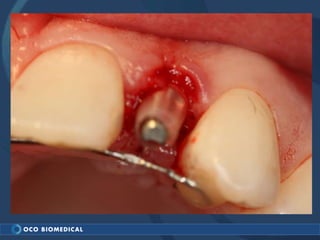

A 3.0mm dental implant was placed to replace congenitally missing maxillary lateral incisors. Dr. Tim Kosinski used a 1.8mm pilot bur and tissue punch to prepare the osteotomy site, then placed the implant by hand and seated it with a torque wrench. After ensuring the implant trajectory was within the restorative envelope, an acrylic coping was placed for temporary fabrication. At the 1 week post-op appointment, excellent soft tissue response and papilla formation were observed, and a final impression was taken to send to the lab for crown fabrication.